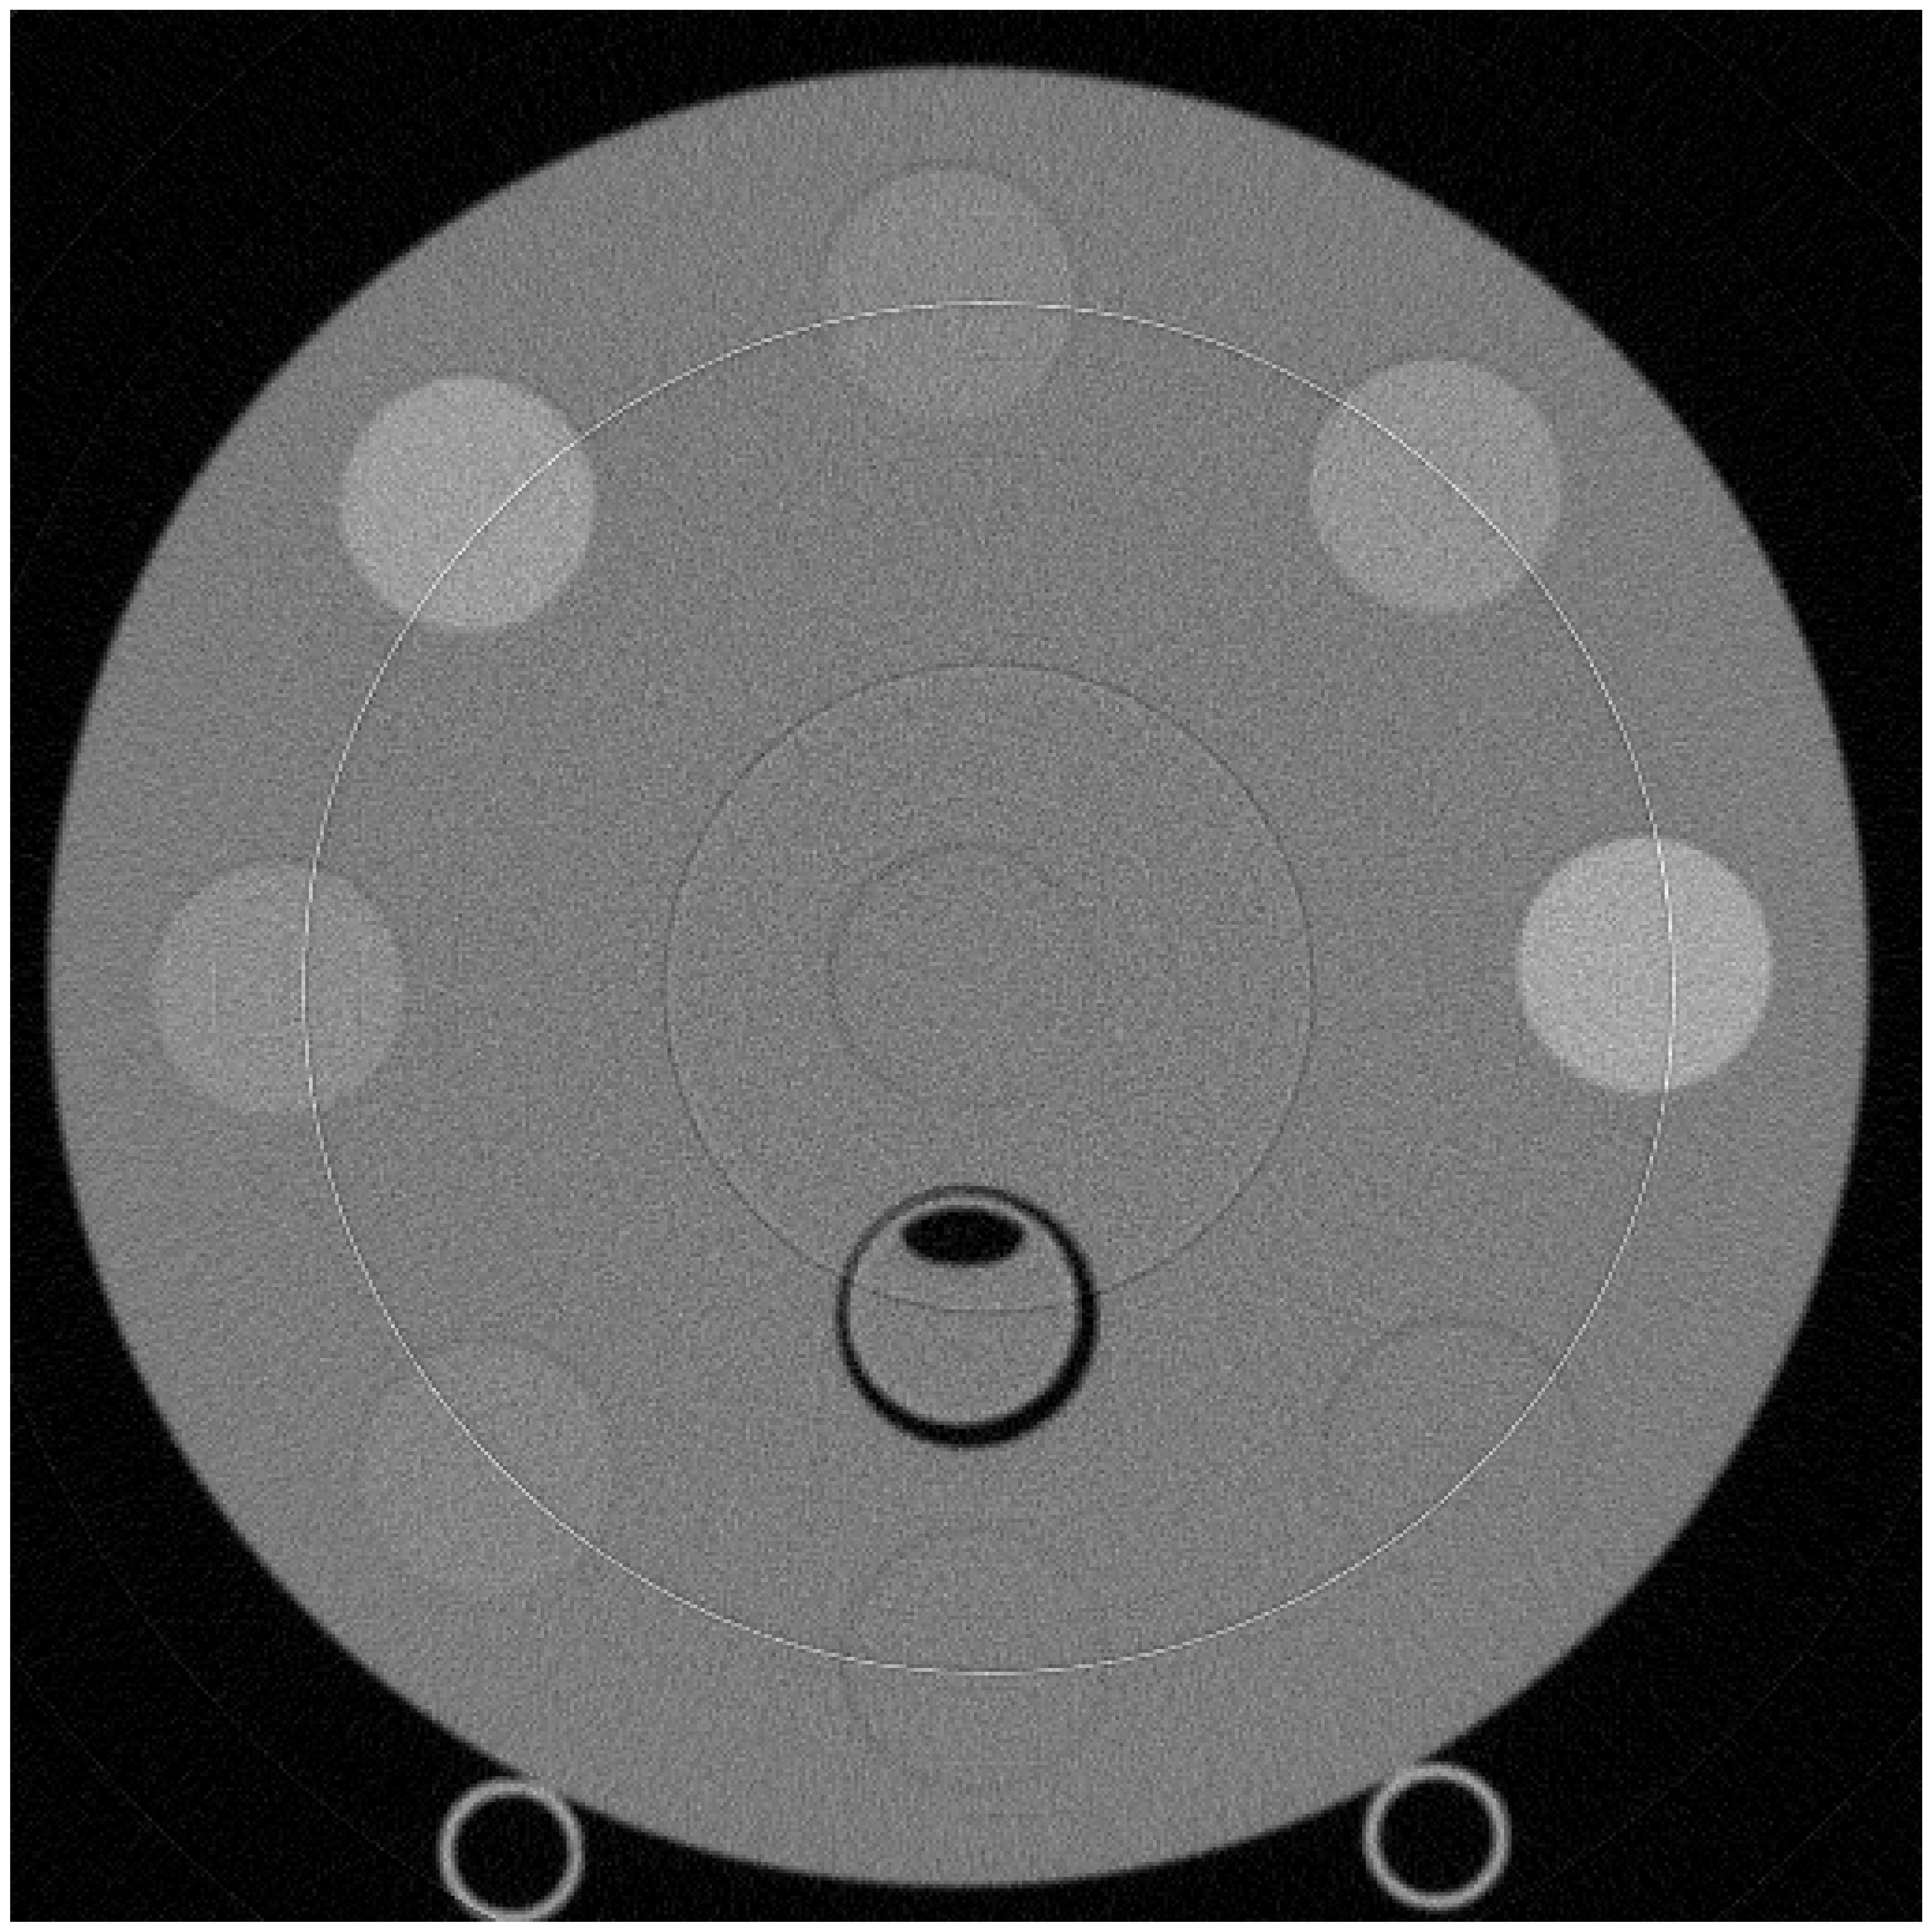

For experiments with measured data, we used data obtained from scans of the Gammex Multienergy phantom, without the body ring. This phantom contains iodine inserts with various densities. The DFOV is 40 cm which is then cropped to a size of to show just the relevant region.

Figure 3 shows a reconstruction, from actual measured data, for the same phantom with the proposed algorithm (bottom row) as well as a comparison to the calculated MLE (top row). The MLE estimates are obtained with to ensure convergence. The proposed method also employs MLE estimate to initialize . However, in this case, we found to be sufficient, saving the computation time. This demonstrates that we can reduce the number of iterations needed to calculate an approximate value for the MLE while still achieving significant noise reduction. For the prior model to denoise the measured data, we decorrelate the PE and PVC pathlength sinograms by rotating these in material space and applying Gaussian filters of standard deviation 6.0 and 1.5, respectively. We then rotate the pathlength sinograms to their original orientation. Lastly, we clip the values to the limits of the calibration space. Note that this is a more complex denoiser compared to that applied to the simulated data. This demonstrates the modularity of our method with the ability to mix and match denoisers depending on application. Figure 3 shows a visual comparison in noise between the MLE and the MACE results.

Figure 4(a) labels circles used for quantitative evaluation. Table 1(a) shows the means and standard deviations for the selected circles. As expected from Figure 3, our method shows a similar mean but a significant reduction in standard deviation compared to the MLE quantitatively.

Figure 3 reconstructions have thin, bright and dark concentric rings, which are artifacts due to limitation of the detector prototype employed. These measurements are removed in practice, but such removal is not part of this proposed method. Importantly, the proposed method gives flexibility to scale the parameter in a band around these detector elements to remove such artifacts, but the fine tuning of is not performed in these results.